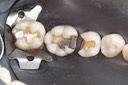

Alan Chinn #3 pre-op

Alan Chinn #3 caries removal 2